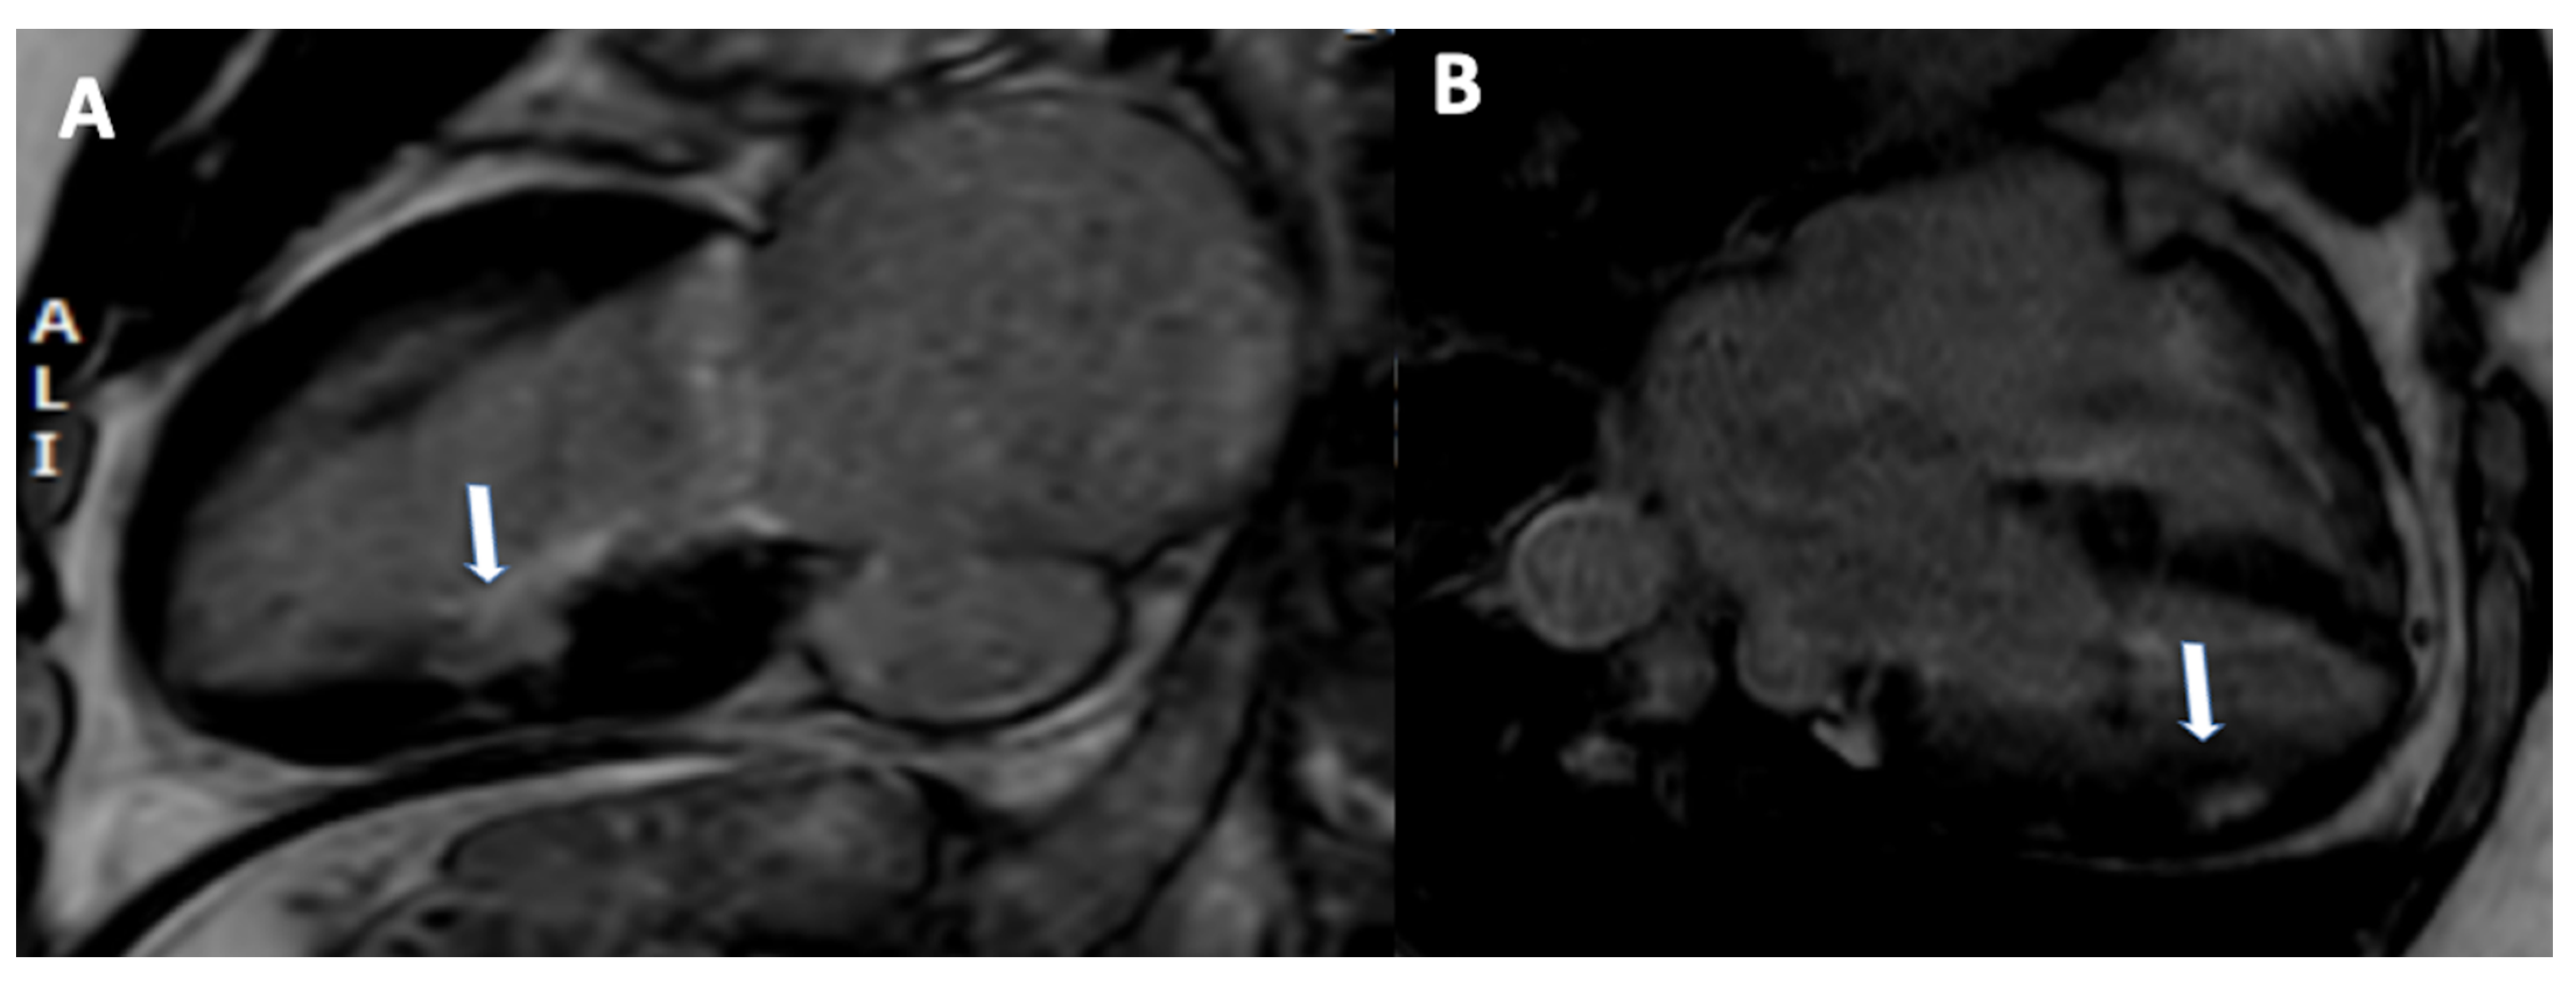

The main disadvantages of stress-CMR perfusion are its low availability and the high level of expertise required. On the other hand, because of its clinical advantages, lack of ionizing radiation, and low cost, it is a radiological technique that will be used more frequently in the future to study myocardial ischemia, especially considering a more quantitative approach. Furthermore, it could represent a useful tool for the functional assessment on top of CCTA in presence of CAD that requires the evaluation of myocardial ischemia. A case of stress CMR is shown in Figure 4.

Figure 4.

A 65-year-old male patient with known history of chronic total occlusion of right coronary artery, moderate stenosis on left anterior descending artery and mild stenosis on right coronary artery. Rest perfusion sequence does not show any significant defect of perfusion (A). During stress acquisition, a deficit of perfusion was observed in the septum and inferior wall ((B), arrows).